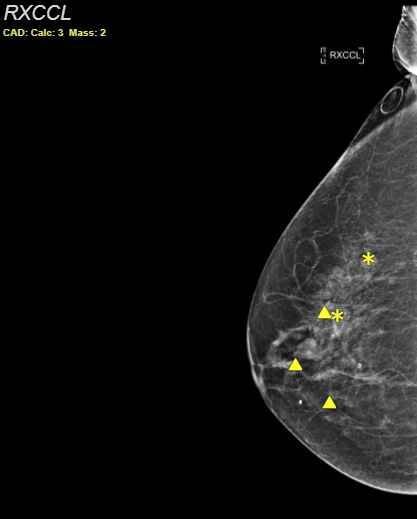

Mammography CAD objects

SUITESTENSA supports the display of Mammographic Computer-Aided Detection objects.

CAD markers are displayed on the image. See the Mammo CAD markers and outlines table below for information on what each marker means.

Mammo CAD markers and outlines

Note that CAD outlines can be enabled or disabled by administrators. Certain vendors may not display markers or outlines for CAD objects. See Vendor-specific display below for more information.

Figure 1 : CAD marker (left) and CAD outline (right)

Calcification cluster |

Individual calcification |

Mass (density) |

Mass with calcifications |

Mammo CAD indicators

| CAD: Calc: 2 Mass: 1 |

CAD markers displayed Shown in the viewport to indicate that CAD markers are displayed. The numbers represent the count for every type of displayed marker. |